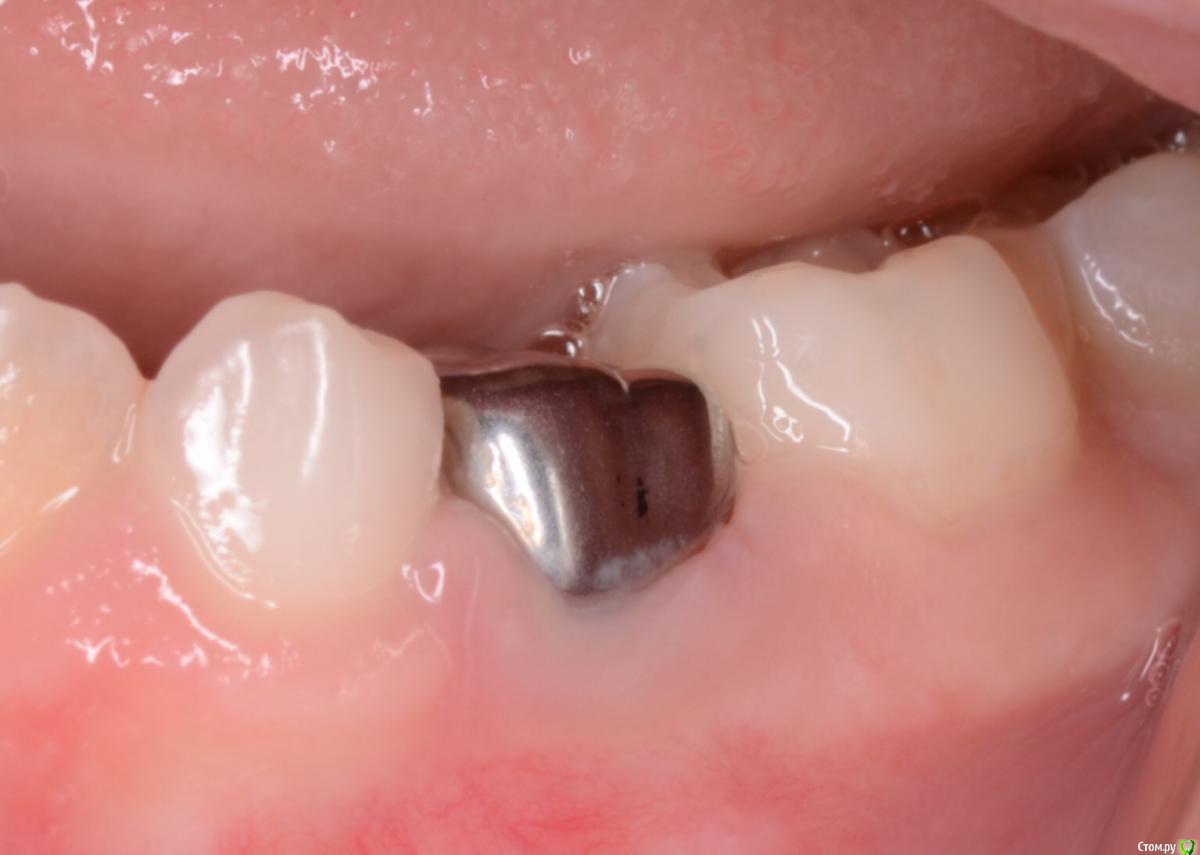

CRAZYDUCK Опубликовано 7 июня, 2018 Автор Поделиться Опубликовано 7 июня, 2018 Восстановление десны после фиксации коронки происходит примерно за неделю . Ниже фото в день фиксации и через 10 дней . 1 Ссылка на комментарий